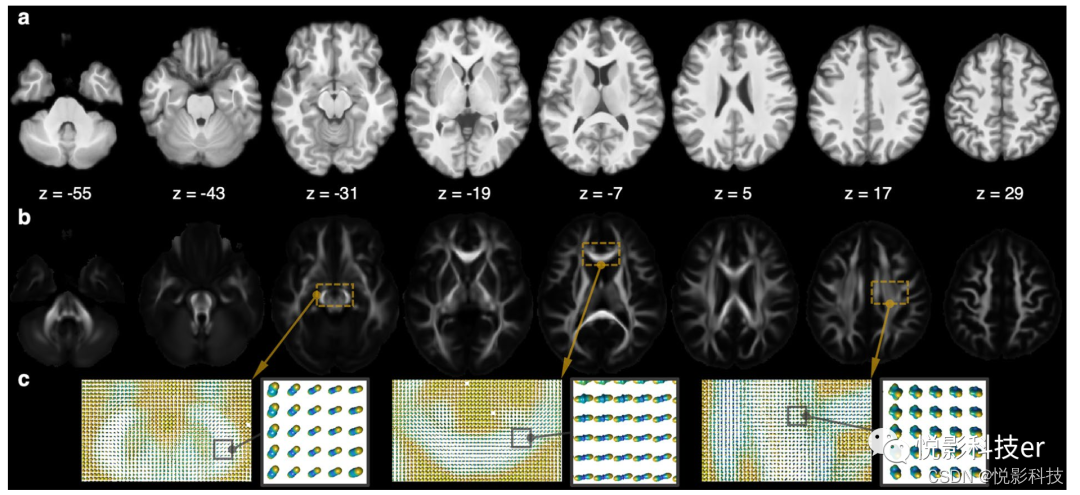

3.1 结构核磁和HARDI图集

图3显示了结构t1加权图(图a)和HARDI GFA(图b)。GFA,类似于FA,表征了相对于单位球的白质纤维分布的整体形状。GFA值越大(最大值为1)表示光纤取向越复杂,而GFA值为0则表示ODF为球形。图3c显示中脑ODF、胼胝体、上纵束(SLF)。前两个显示同步的纤维取向,最后一个显示交叉的纤维在SLF。

图3 结构图集